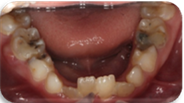

8岁女孩后牙区反复肿胀近半年未经治疗,咬物偶有疼痛

65MO深大龋洞,色棕黄,质软,叩痛(+),不松动,牙龈红肿,未见瘘管。 X线片示:冠部低密度影达髓腔,根分歧区大面积低密度影,近远中根内侧壁见吸收。25牙胚存,未拍全。 64MO深大龋洞,色棕黄,质软,叩痛(+),不松动,牙龈略红肿。 X线片示:根分歧区密度减低。 84OD深大龋洞,色棕黄,质软,叩痛(-),不松动, 85MO牙色充填体周围见龋坏,色黑,质软,叩痛(±),不松动,龈无异常。 X线片示:根周见低密度影,44,45牙胚存,未拍全。 54DOL深大龋洞,色黑,质软,叩痛(-),不松动, 55O窝沟色黑,卡探针,叩痛(-),不松动,龈无异常。 74OD,75MO半年前曾于外院行充填治疗,现检查见充填体边缘色黑,卡探针,充填体略有松动。